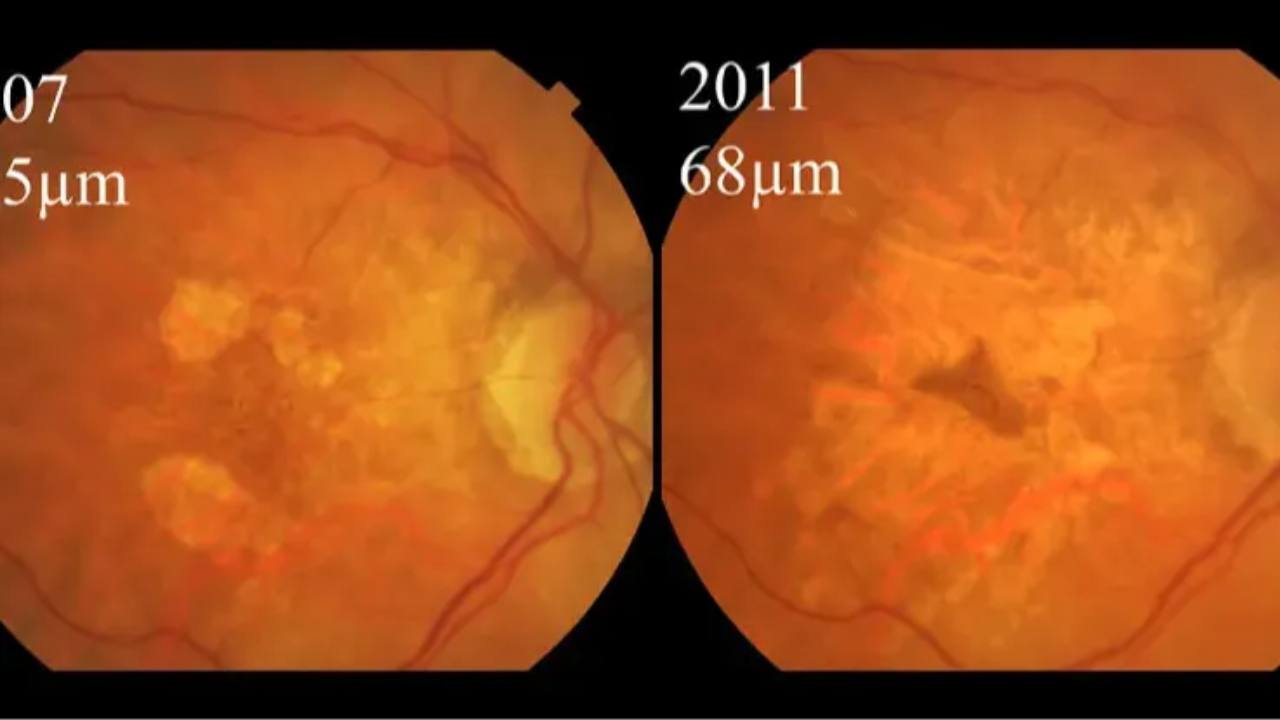

Geographic Atrophy & AREDS

Does supplementation matter?...

A study published in Ophthalmology has found promising results in the management of a particular subtype of age-related macular degeneration (AMD). Oral antioxidant and lutein/zeaxanthin supplements, specifically the AREDS2 formulation, have demonstrated signific...